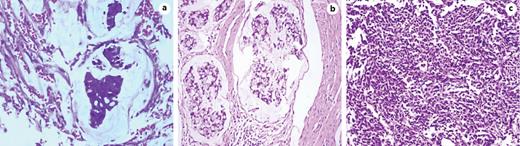

The average size of urachal tumors was 3.9 cm (range: 1.3–8.0 cm, the resected specimen shown in Fig. 2). Of 59 urachal cancers, the tumor was located in the dome of the bladder in 47 cases (76.09%) and at the anterior wall of the bladder in 10 cases (21.74%) (2 cases were multiple tumors). Histologically, 19 cases were adenocarcinoma not otherwise specified (NOS), 19 cases were mucinous adenocarcinoma, 5 cases were adenocarcinoma with mucinous adenocarcinoma, 5 cases were mucinous adenocarcinoma with signet ring cells, and 2 cases showed adenocarcinoma mixed with signet ring cells and mucous cells or enteric differentiation. Only 1 case showed pure signet ring cell subtype, and 5 cases exhibited enteric adenocarcinoma. Two cases were small-cell carcinoma and 1 case was transitional-cell carcinoma with adenomatous metaplasia (shown in Fig. 3a–c). Lymph node invasion was present in 6 patients. The positive surgical margin, defined as tumor cells were seen microscopically at any part of the proximal cut edge of umbilical ureteral or resection margin of bladder, was seen in 2 cases.

a Urachal adenocarcinoma, mucinous type. b Urachal adenocarcinoma, signet ring cell type. c Urachal small cell carcinoma (HE.; original magnification ×200).